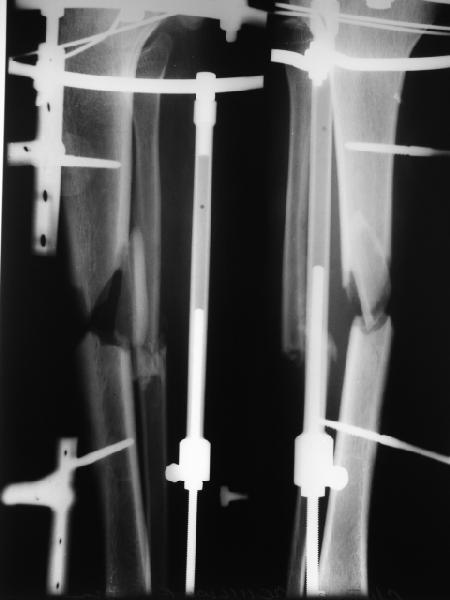

Вот пример, тоже открытый перелом, первичный дефект, пробыл в аппарате 5 мес. Титановый гвоздь, сразу динамический, без покрытия. Больше не делали ничего.